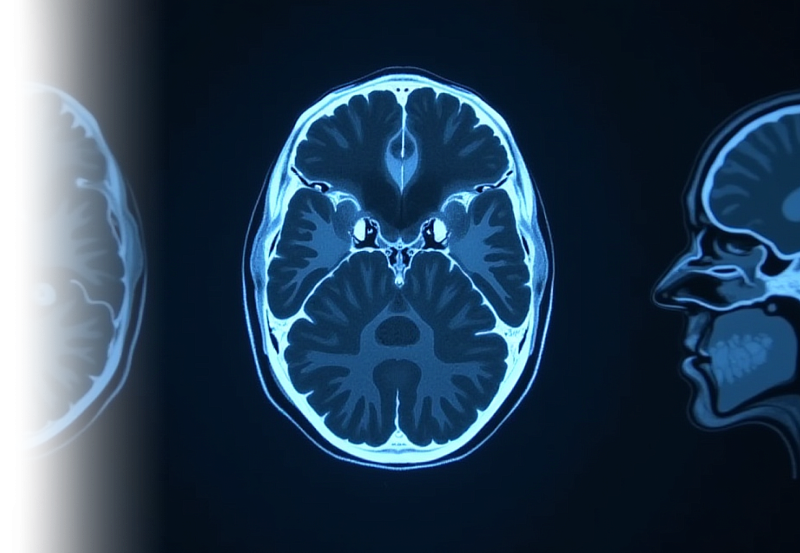

КТ головного мозга

Компьютерная томография головного мозга – важный метод исследование, которое позволяет получить детальное представление о состоянии головного мозга.

КТ позволяет оценить вещество мозга на наличие ишемических изменений, образований вещества мозга, внутримозговых и оболочечных гематом, а также анатомию мозга.